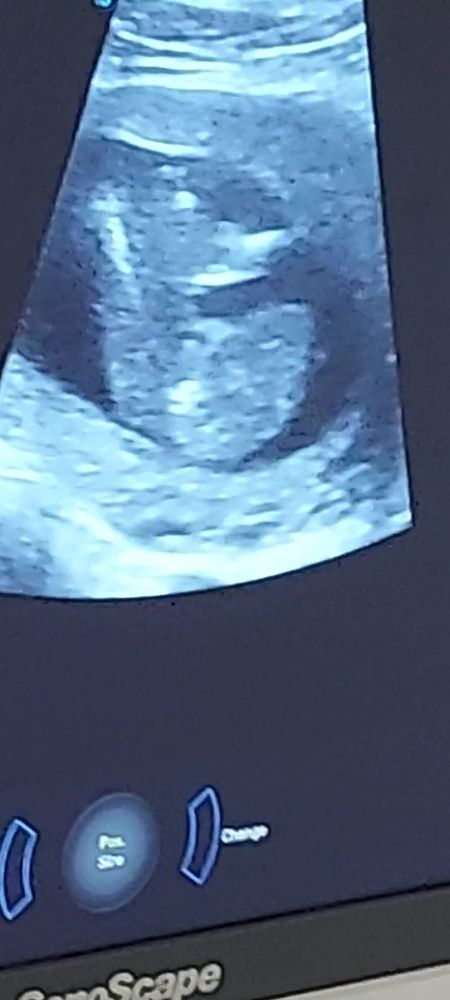

Сегодня узнаем кто в домике живет) (много фото узи) а вы как думаете?)

Плохое качество фото, видно что все они сняты между ног, но не чётко, вообще яичек нет вроде бы, значит девочка.

УЗИ 12 недель Точно девочка?)